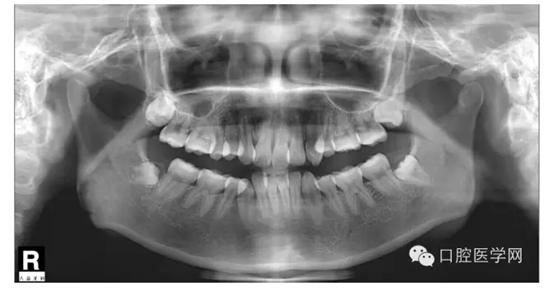

這是一位我同事接診的一位患者,成年女性,安氏II類,高角,下頜后縮,重度深覆合,上下中線右偏,原本做過一次矯正,4個(gè)4已經(jīng)拔除。

我同事又給她拔了左邊兩個(gè)5,然后我同事離職了,把患者扔給我。

所以這個(gè)患者我選擇使用弓絲壓低下前牙。但由于雙尖牙只剩下15,45,所以我們將37,47,納入矯正。